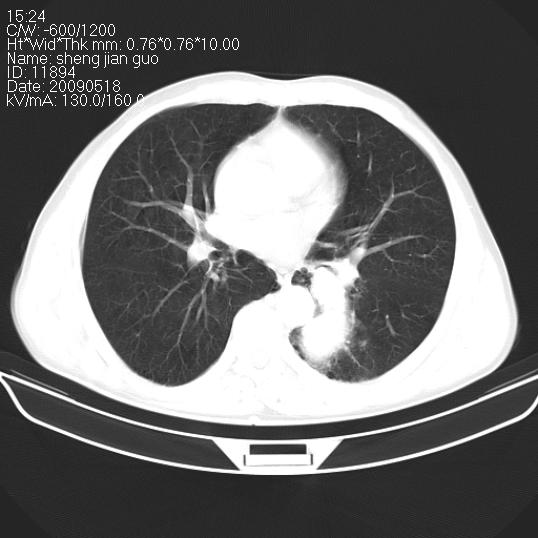

以下是引用zjzjr在2009-5-19 17:25:00的发言:[br]支持楼主考虑,另左肺下叶阻塞性炎症。

以下是引用zhao_bin2008在2009-5-19 17:48:00的发言:[br]支持左肺下叶周围型肺癌并阻塞性肺炎。

以下是引用zsl6918在2009-5-20 7:10:00的发言:[br]左侧中心型肺癌!